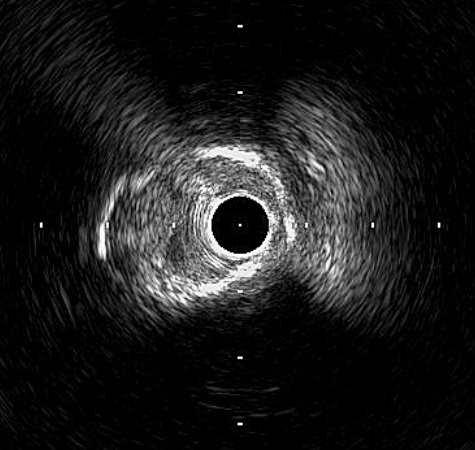

Intervention of RCA Right Coronary Artery was engaged with JR 7Fr Guiding Catheter. Lesion was successful wired with Fielder XT-R and was changed back to workhorse (NS Runthrough) wire. Sequential predilatation using 1.0/15 Sapphire, 1.5/15 Sapphire II Pro, and 2.25/15 Sapphire II Pro was then carried out with Guideplus II assistance; unfortunately, severe balloon underexpansion was noted. Rotational Atherectomy (RA) was attempted 1.25mm Burr for 2 passes at 180k rpm. Lesion was further prepared with 3.0/13 NSE Aperta and 3.0/10 NC Sapphire 24 under Intra-vascular ultrasound (IVUS) guidance before deploying overlapping 3.0/40 Orsiro Mission, 3.5/40 Orsiro Mission and 4.0/18 Orsiro Mission. Repeat IVUS after stent optimization showed stent underexpansion. Hence, intravascular lithrotripsy (IVL) was performed with Shockwave 3.5/12 for a total of 80 shocks, followed by 3.0/10 NC Sapphire stent optimization.